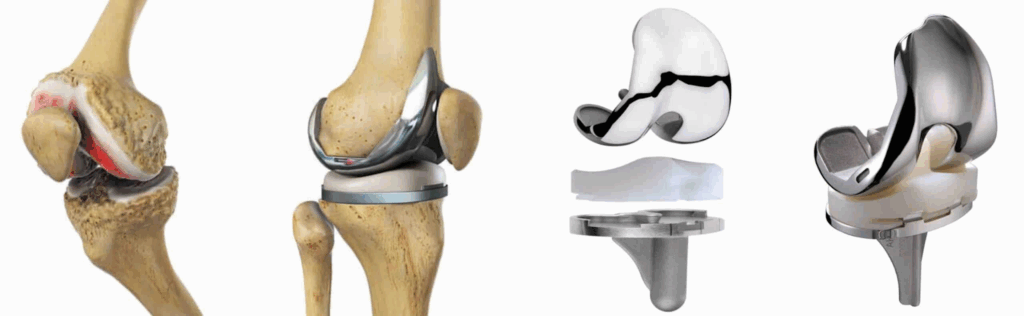

- Prótese de joelho: substitui a articulação desgastada por uma artificial.